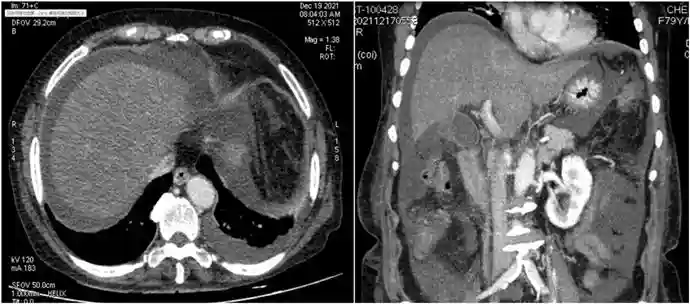

胃肠道间质瘤(GIST)